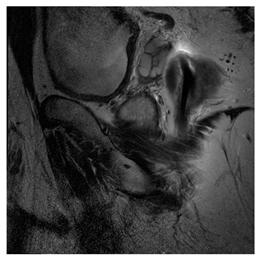

(e)

Prostate-MRI Database (available at: https://wiki.cancerimagingarchive.net/display/Public/PROSTATE-MRI (accessed on 4 November 2021))

Prostate-MRI database contains MRI-type medical images and collects prostate medical images. Some samples are shown in Figure 12e.

Figure 12. Sampled images in the tested benchmark databases: (a) Breast-MRI-NACT-Pilot (breast), (b) ACRIN-DSC-MR-Brain (brain), (c) NIH (chest), (d) Lung-PET-CT-Dx (lung), (e) Prostate-MRI (prostate), and (f) Other grayscale standard images.